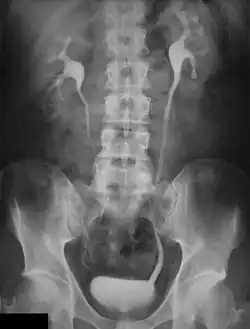

Intravenöses Urogramm

Urografie oder Urographie (altgriechisch οὖρον ouron „Urin“ und -graphie), synonym Pyelographie (altgriechisch πύελος pyelos „Wanne, Trog“, hier: „[Nieren-]Becken“), sind radiologische Methoden zur Darstellung der ableitenden Harnwege (Nierenbecken, Harnleiter und Harnblase). Die erzeugten Aufnahmen werden Urogramm beziehungsweise Pyelogramm genannt.

Diese Verfahren dienen zur Darstellung von Morphologie und Funktion der Nieren und der ableitenden Harnwege sowie zur Feststellung von Abflussbehinderungen, etwa durch Harnsteine. Uratsteine (Harnsäuresteine) sind röntgennegative Steine, das heißt, sie lassen sich im Röntgenbild nicht direkt darstellen.

Bei der retrograden Urografie (auch retrograde Pyelografie genannt), entwickelt durch Friedrich Voelcker und Alexander von Lichtenberg, Heidelberg 1905,[1] und bei dem Miktionszystourethrogramm wird eine Kontrastmittellösung über einen Blasenkatheter in das Hohlsystem instilliert. Zur sogenannten intravenösen Urographie, auch Ausscheidungsurographie (erstbeschrieben durch Volkmann 1922) genannt, werden ca. 50 ml eines jodhaltigen Röntgenkontrastmittels in eine Armvene injiziert und die Ausscheidung wird in einer Serie von Röntgenaufnahmen von Bauch und Becken verfolgt. Je nach Grad der Abflussbehinderung dauert das zwischen 15 Minuten und 24 Stunden.